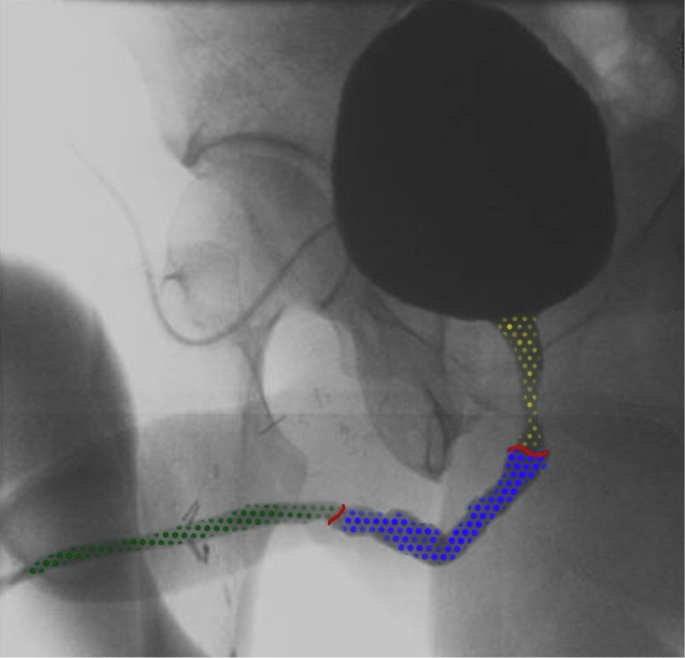

To provide a clearer understanding of the outcomes from various studies, Fig. 2 presents an example of UL anatomy following phalloplasty, while Fig. 3 illustrates examples of urethral complications. Several urethroplasty techniques were employed across studies, including single-stage [9, 17, 18] and staged repairs [19, 20], buccal mucosa graft urethroplasty (BMGU) [7, 17, 21], excision and primary anastomosis (EPA) [22], pedicled flaps [23], Heineke-Mikulicz procedure (HMP) [23,24,25] and ventral meatotomy [26].

In this systematic review, we analyzed a total of 585 urethroplasty procedures performed primarily in transmen, mostly following phalloplasty, with a smaller number occurring after metoidioplasty. In rare instances, outcomes of urethroplasty in cisgender men were included in the reported data. The urethra in phalloplasty is often constructed using a combination of local mucosal flaps for the pars fixa and skin flaps or grafts for the pars pendulans, creating a structure composed of different types with varying supportive tissues and healing capacities. The urethra in metoidioplasty is often constructed using a combination of local mucosal flaps, with adjunction of BMG or vaginal mucosa graft; this approach closely resembles the construction of the pars fixa in phalloplasty. The main complications arise from the distal urethral anastomosis and the pars pendulans, where skin is commonly used. In contrast, BMG is the preferred graft material for redo urethroplasty [28].